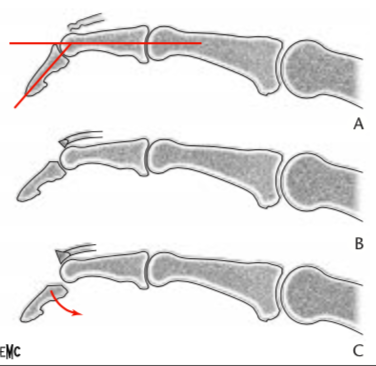

Le doigt en maillet, ou Mallet Finger, est une rupture du tendon extenseur au niveau de son insertion sur la dernière phalange.

L’atteinte concerne le tendon extenseur au niveau de la bandelette terminal.

Elle peut parfois s’accompagner d’un petit arrachement osseux.

Lorsque ce tendon rompt, la phalange distale bascule en flexion et ne peut plus se redresser.

Selon qu’il s’agisse d’une rupture tendineuse pure ou d’un fragment osseux arraché, la stratégie de traitement reste similaire dans la majorité des cas.